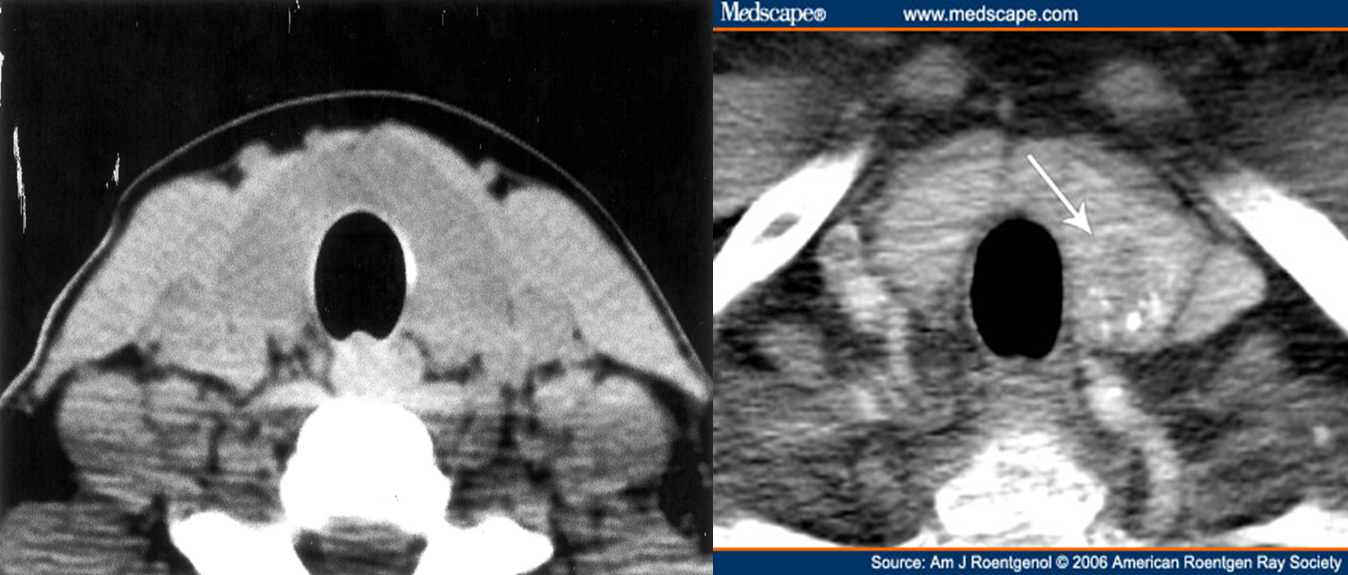

is not often used to examine the thyroid except to demonstrate the extent of a retrosternal goitre and for the assessment of any local mass effect, such as tracheal compression

CT shows clear anatomy of thyroid gland